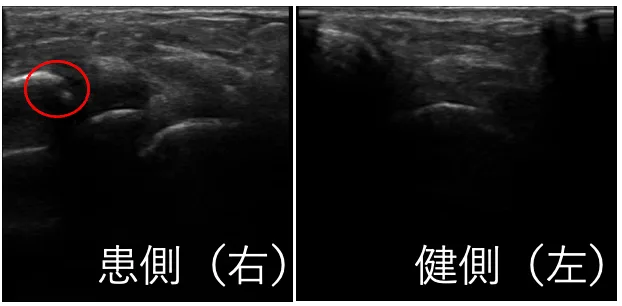

エコー検査でも骨折像が確認できたので、取り外しのできるギプス固定と、LIPUS(超音波骨折治療器)を行いました。